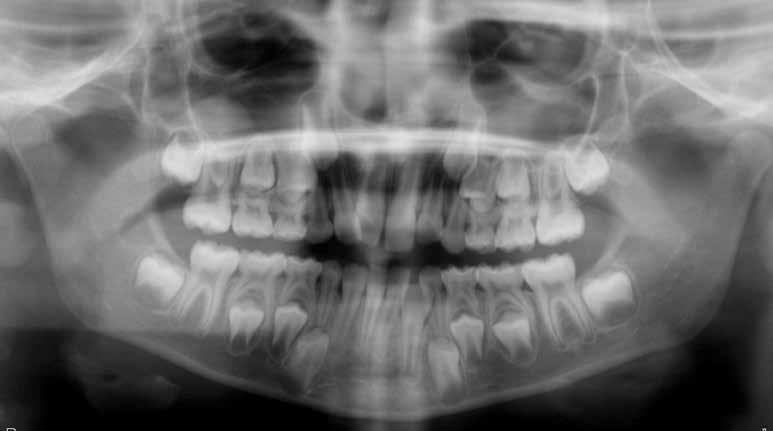

47 46 ESTETICA FUNZIONE POSTURA Valori cefalometrici a 10 anni : ANB ANB 2.70 Posizione del Mascellare SNA 78,70 Posizione della Mandibola SNB 76.0 Angolo Articolare SArGo 142,76 Angolo Goniaco ArGoMe 125,73 Angolo incisivo inf^Corpo madibolare IiMand 92,00 Angolo incisivo Sup^Base Cranica Ant. IsCran 96,00 Angolo Interincisivo II 130,0 53 _ Esame Cefalometrico a dieci anni. 54 _ Tabella dei valori cefalometrici a dieci anni. 55 _ Ortopantomografia di controllo a dieci anni. 56 _ Teleradiografia di controllo con evidente stabilità del caso dal punto di vista scheletrico/posturale.

> La documentazione a dieci anni mostra la stabilità del caso e

come l’occlusione, elastodonticamente individuata, costituisca anche la contenzione stessa. La paziente ha smesso di

Considerazioni

indossare l’apparecchio elastodontico dopo due anni e mezzo di terapia, conservando parametri occlusali e posturali in rapporto corretto tra loro.

Nel 2019 si è provveduto all’avulsione chirurgica degli elementi dentari 18, 28, 38 e 48.

Alla risoluzione della malocclusione scheletrica e dentale si associa un netto recupero della postura con conseguente miglioramento della curva cervicale, come è possibile verificare nella teleradiografia finale.

Ortopantomografia iniziale. 60 _ Tracciato cefalometrico ad inizio terapia. 61 _ Valori cefalometrici ad inizio terapia.

Considerazioni > L’analisi cefalometrica ad inizio trattamento dimostra la II Classe scheletrica con protrusione del mascellare superiore e prognazia mandibolare; tendenza alla crescita verticale. L’esame clinico evidenzia una protrusione mandibolare funzionale.